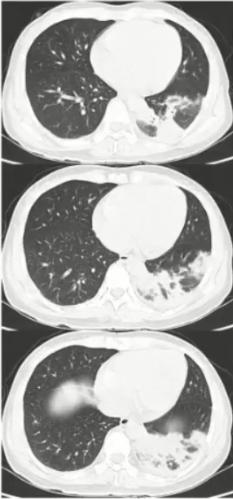

图2 影像表现以多发肺结节合并晕征,类似于真菌感染

病例2

男性,33岁,既往身体健康,发热6天入院,无咳嗽、咳痰、咯血、呼吸困难。

日最高体温38.4℃,伴头痛、全身乏力,肺CT示双肺多发结节影,予头孢克肟、美洛西林舒巴坦、布洛芬、奥司他韦等治疗效果欠佳。

血常规WBC 10.63 G/L,N 0.816,L 0.101。CRP 7.42mg/dl,肺炎支原体抗体<1:40,SARS-CoV-2核酸及抗原筛查试验(-)。

入院后情况

• 肺炎支原体抗体1:320

• 左氧氟沙星0.5 QD 口服治疗后体温正常